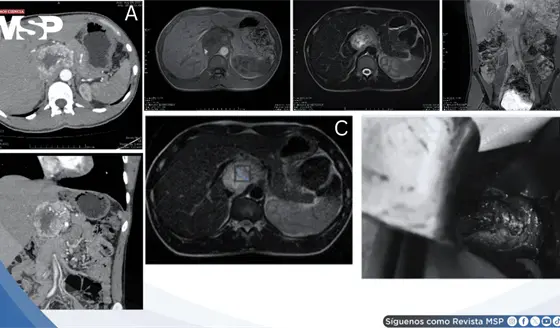

Cefaleas, palpitaciones e hipertensión severa revelan paraganglioma funcional portocava de 7,2 cm

Enero 26, 2026